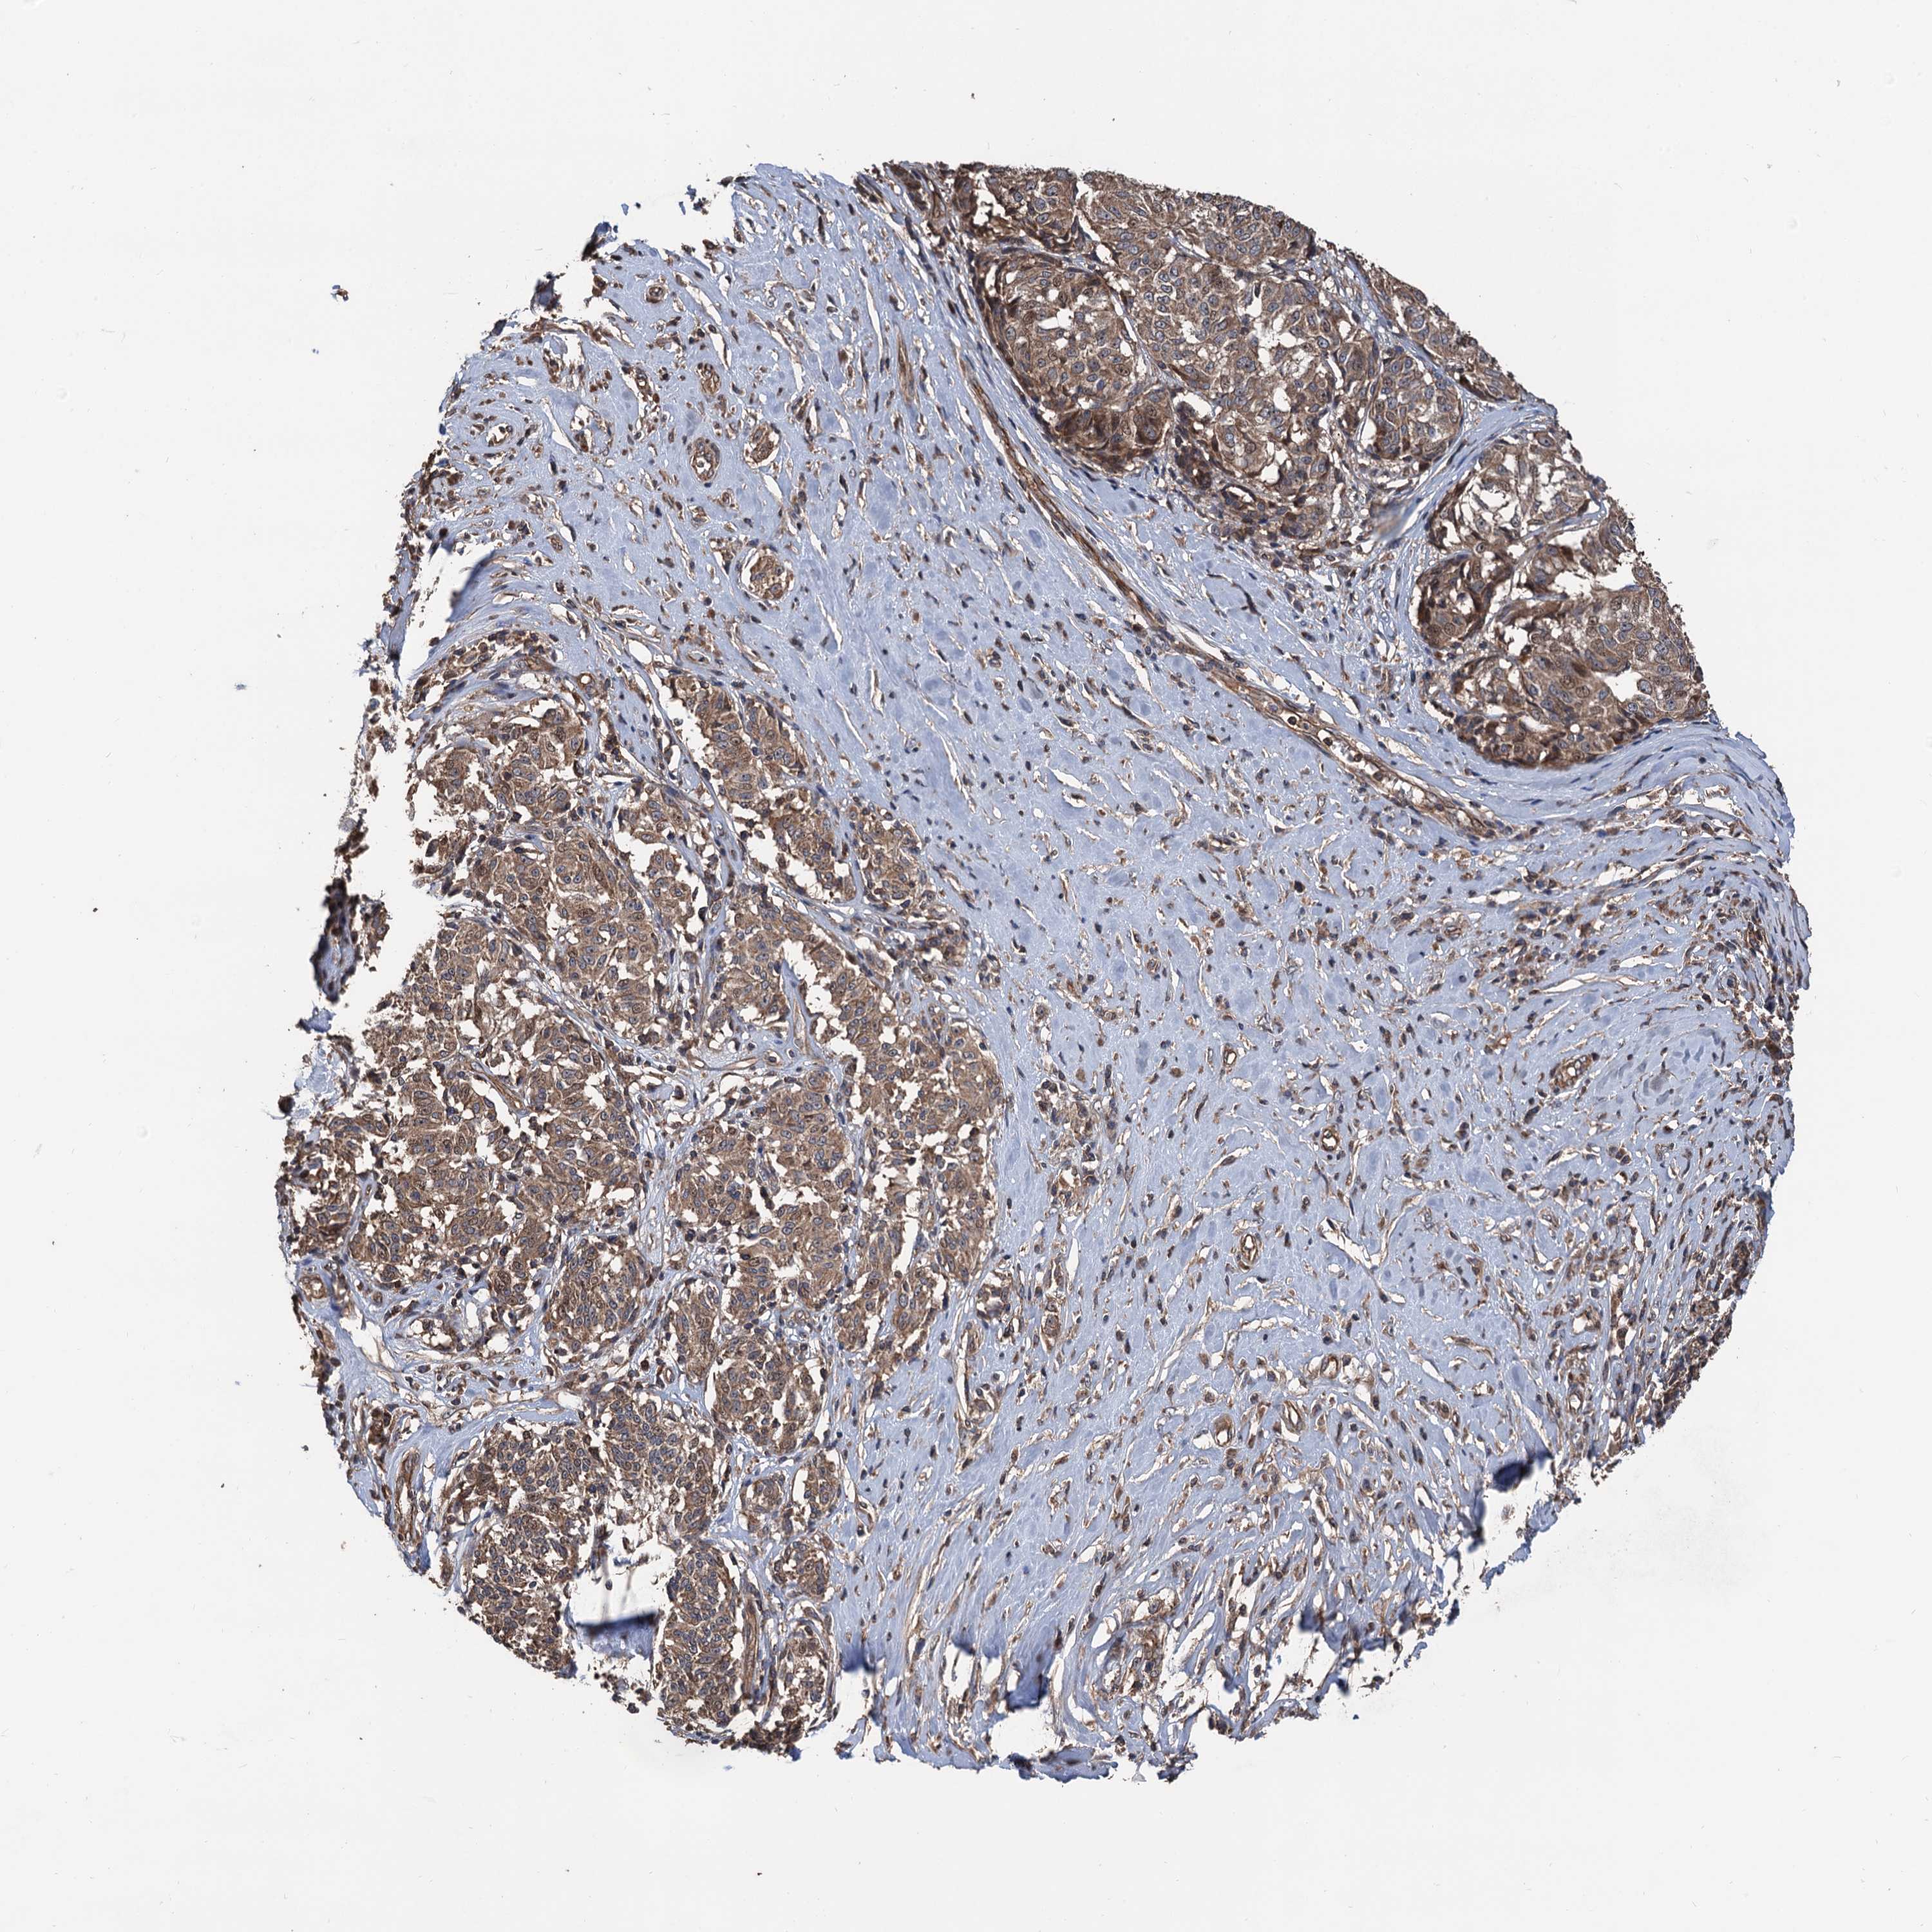

MELANOMA - Protein expressioni

A mouse-over function shows sample information and annotation data. Click on an image to view it in a full screen mode. Samples can be filtered based on level of antibody staining by selecting one or several of the following categories: high, medium, low and not detected. The assay and annotation is described here.

Note that samples used for immunohistochemistry by the Human Protein Atlas do not correspond to samples in the TCGA dataset.

Antibody stainingi

Antibody staining in the annotated cell types in the current human tissue is reported as not detected, low, medium, or high, based on conventional immunohistochemistry profiling in selected tissues. This score is based on the combination of the staining intensity and fraction of stained cells.

Each image is clickable and will lead to virtual microscopy that enables deeper exploration of all samples and also displays staining intensity scores, fraction scores and subcellular localization as well as patient and tissue information for each sample.

Antibody HPA040905

Antibody HPA041089

Staining

High

Medium

Low

Not detected

Intensity

Strong

Moderate

Weak

Negative

Quantity

>75%

75%-25%

<25%

None

Location

Nuclear

Cytoplasmic/membranous

Cytoplasmic/membranous,nuclear

Malignant melanoma, NOS

Malignant melanoma, Metastatic site